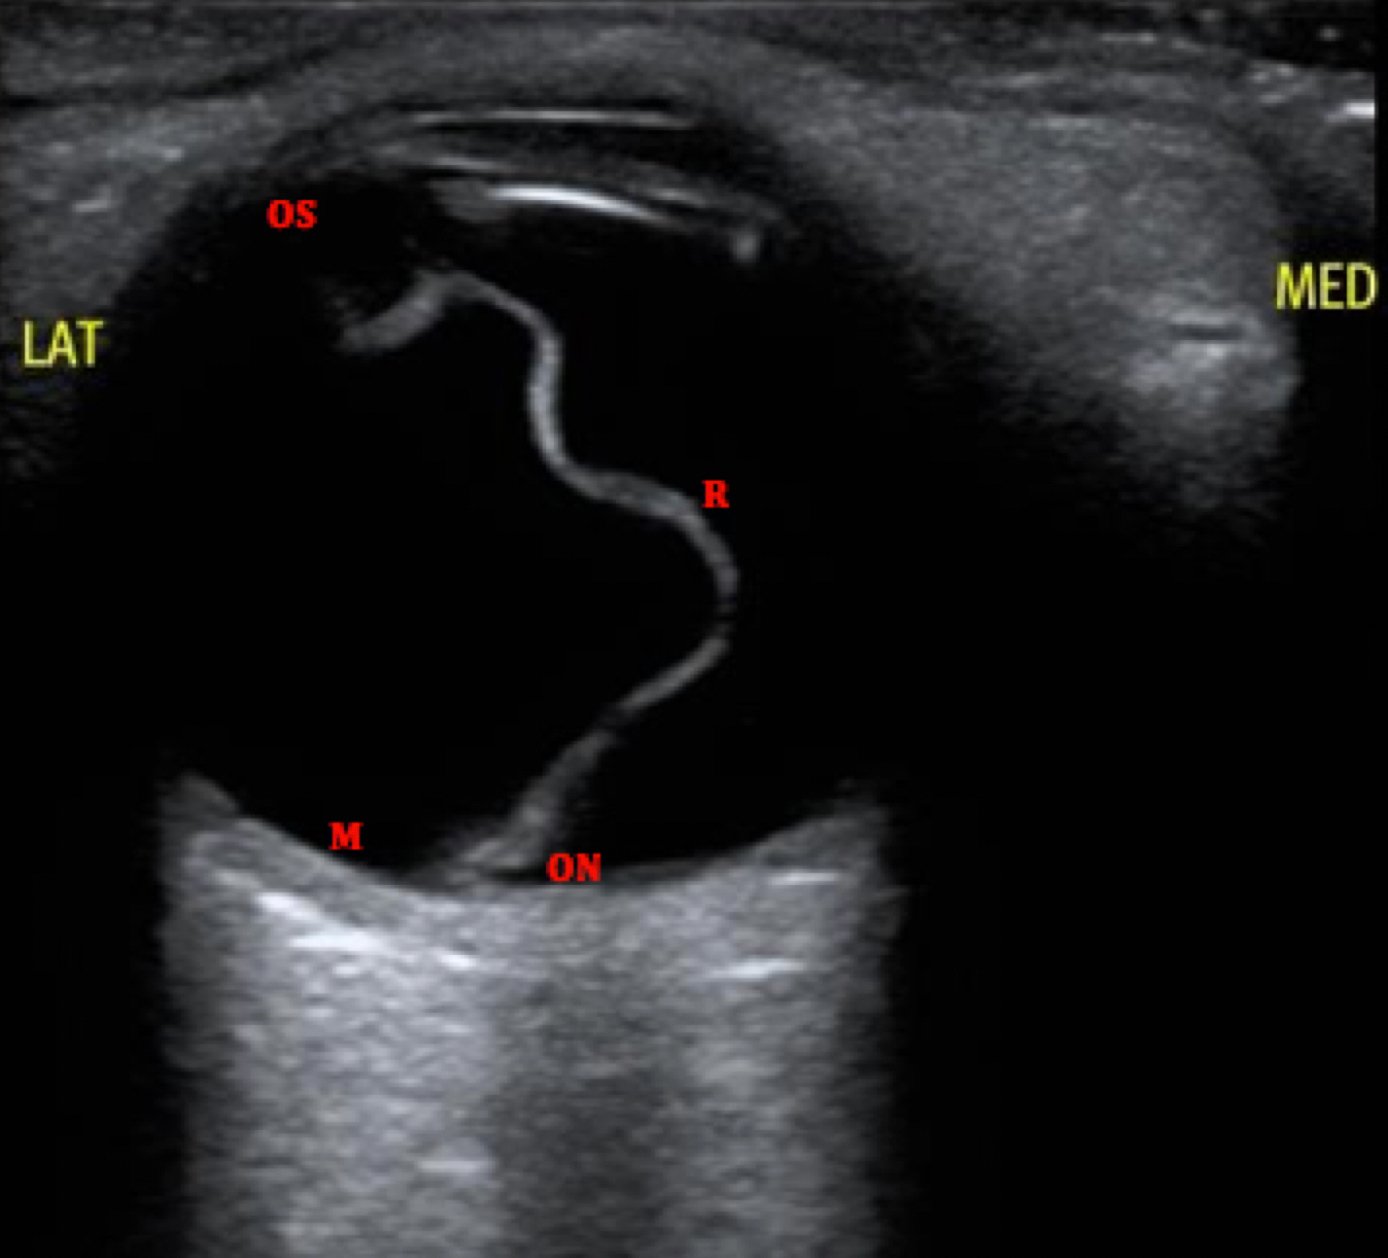

Macula-Off Retinal Detachment. US, Annotated. JETem 2019

Macula-Off Retinal Detachment Identified on Bedside Ultrasound